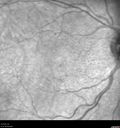

Perifoveal Microaneurysm - Not Diabetic (also reticular pseudodrusen)380 views87 year old female with fluctuating macular edema in the right eye from a perifoveal MA. (no treatment). VA 20/40 OU00000